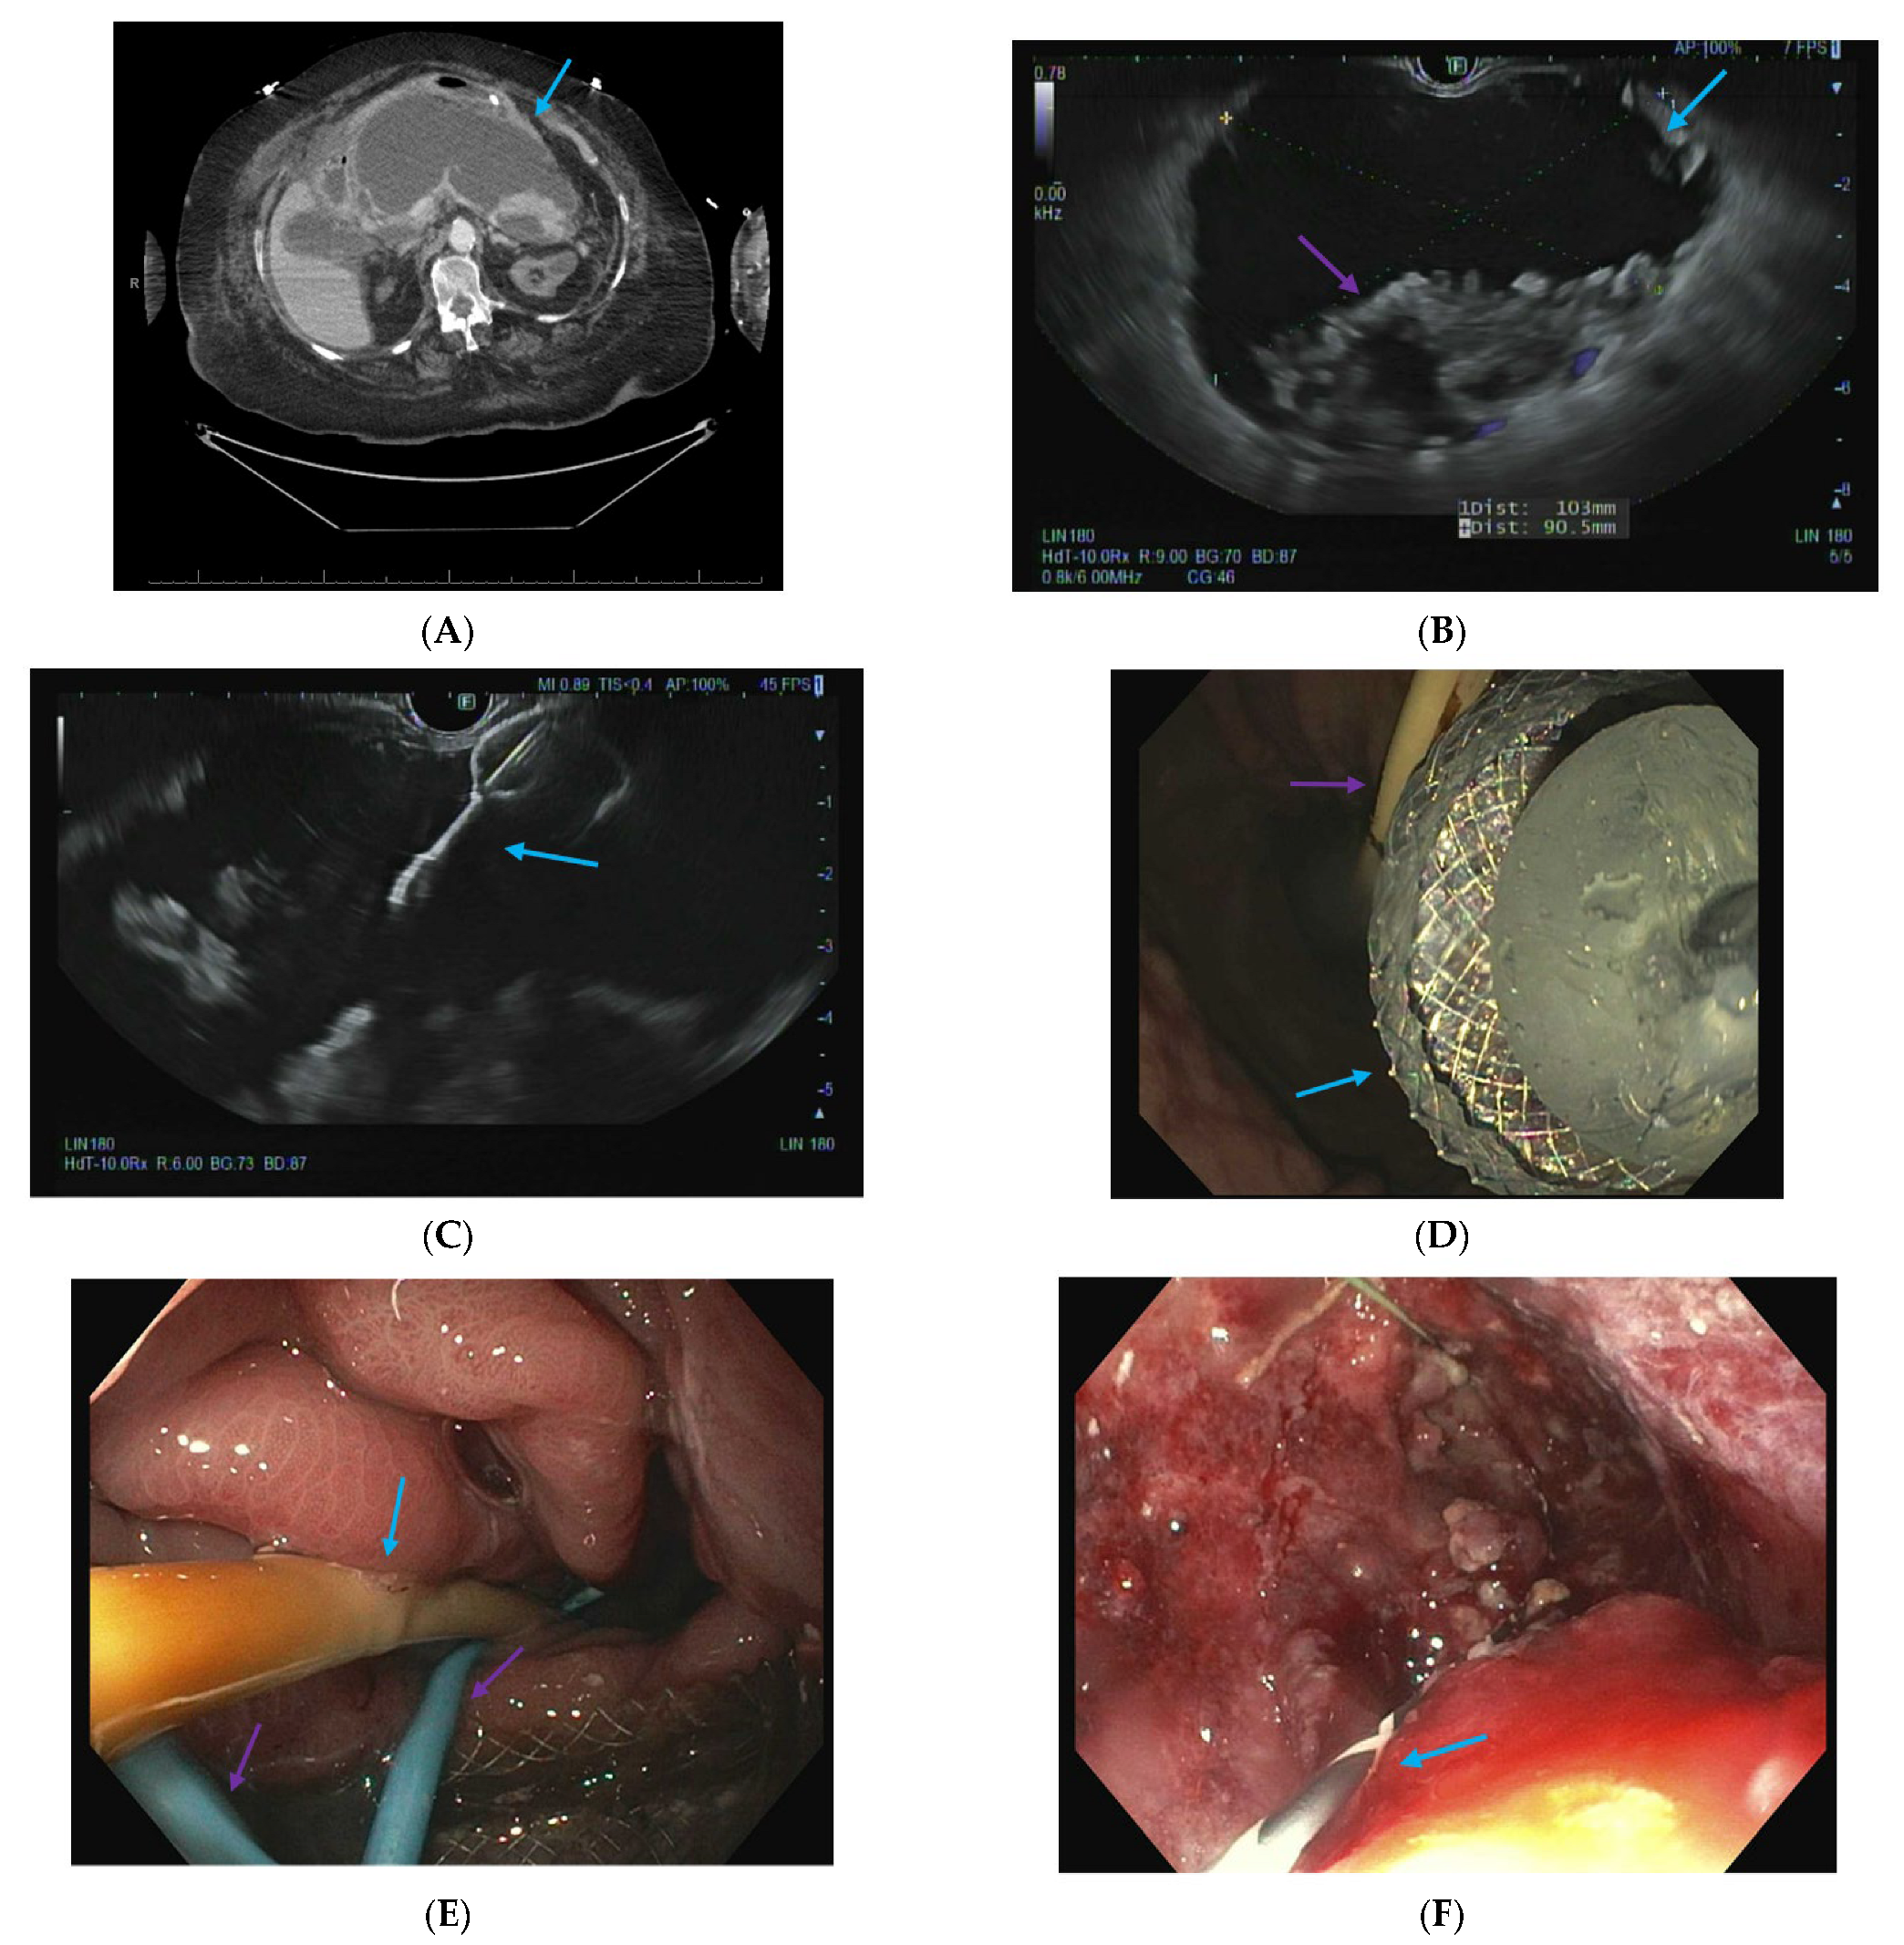

2.3. Infected Pancreatic Necrosis

2.4. Endoscopic Ultrasound-Guided Techniques for Walled-Off Pancreatic Necrosis (WON)

2.5. Direct Endoscopic Necrosectomy

2.6. Dual Modality Drainage

2.7. Interventional Radiology-Guided Embolization of Pseudoaneurysms